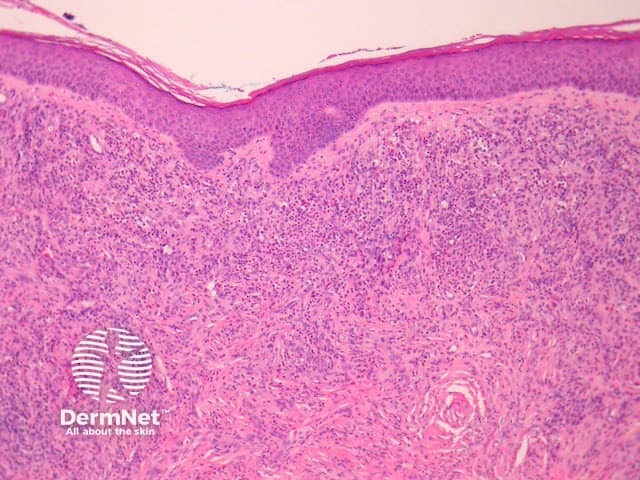

In erythema elevatum diutinum, there is sparing of the papillary and periadnexal dermis (Figures 1, 2). Vascular infiltration in the upper and mid-dermis with predominant neutrophils and fewer lymphocytes, eosinophils and plasma cells (Figures 3, 4, 5). Leucocytoclasia is commonly seen in fresh lesions (Figure 5). Later lesions develop sclerosis with plasma cells and residual foci of leukocytoclastic vasculitis. Sclerosis may be striking and have a storiform pattern (Figures 1, 4).

Figure 1